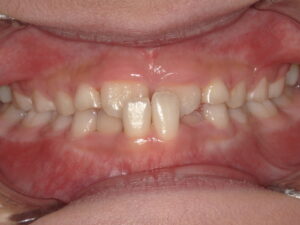

前歯2本の反対咬合 9歳

Before

| 主訴 | 下の前歯が上の前歯より前に出てきた。 |

| 診断名 | 反対咬合 |

| 年齢・性別 | 9歳男子 |

反対咬合では下の前歯が上の前歯よりも前に出ていて、通常の咬合の逆になっています。

今回は骨格的には問題なく、前歯2本の歯の生える向きがずれてしまっているだけなので リンガルアーチにて上の前歯を前に押し出してあげます。

そうすることで下の前歯2本は何もしなくても自然と内側に引っ込みます。